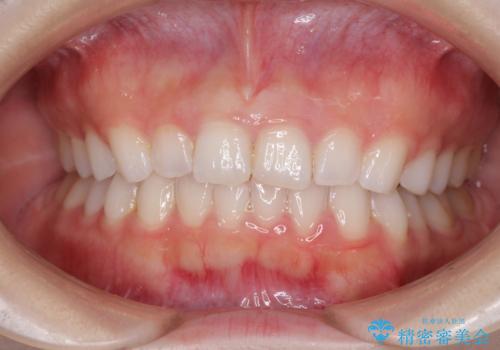

デコボコと深い咬み合わせの改善 インビザラインによる矯正治療

- 口元のデコボコと深い咬み合わせ(ディープバイト)を気にして来院された患者様です。

インビザラインによる上下歯列の拡大と、IPR(歯と歯の間を削る)にるスペースの獲得により、口元のデコボコとディープバイトを改善することとしました。

インビザラインは、装着していない時間がどれだけ短いかが、治療期間を大きく左右します。こちらの患者様は1日22時間以上、毎日欠かさず装着してくださったため、1年強という短期間で満足のいく歯列に整えることができました。